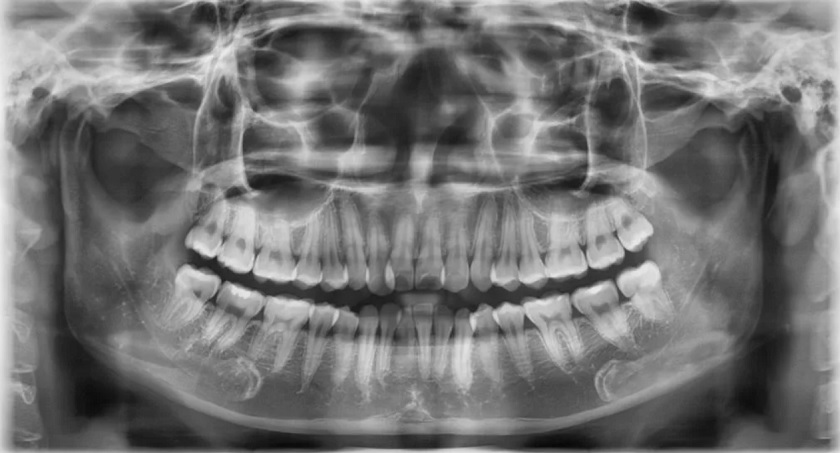

Bởi dù không phải uống thuốc trong quá trình niềng răng, không gây ảnh hưởng đến sức khỏe của mẹ và bé, nhưng trước khi thực hiện vẫn cần tiến hành chụp X-quang để kiểm tra cấu trúc xương hàm cũng như mức độ lệch lạc của răng.

- Trước khi tiến hành niềng răng chỉnh nha, bạn cần phải thực hiện nhiều bước thăm khám và chẩn đoán thông qua chụp X-quang răng.

- Máy móc, trang thiết bị hiện đại, hệ thống chẩn đoán kỹ thuật số Cone Beam CT 3D thế hệ mới giúp Bác sĩ phân tích đúng và chính xác nhất tình trạng cấu trúc răng, xương hàm của khách hàng để có phác đồ điều trị phù hợp.